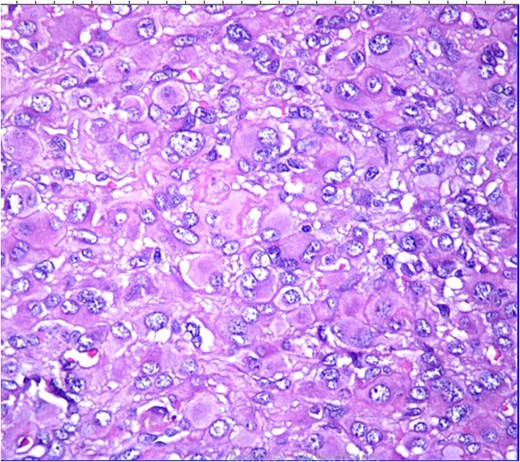

Histopathological analysis revealed a poorly differentiated dermal neoplasm arranged in a solid growth pattern. The tumor cells were epithelioid, with abundant eosinophilic cytoplasm and centrally or eccentrically placed nuclei exhibiting moderate atypia and prominent nucleoli (Figs 1 and 2). The mitotic rate was 4 per 10 high-power fields (HPF). The stroma was fibrous, and the surgical margins were involved. Immunohistochemical analysis showed tumor cells positive for vimentin, CK7, and S100 protein, with a MIB-1 proliferation index of 5%. Negative staining for cytokeratin, androgen receptors, PHLDA1, and p63 excluded adnexal tumors. Additionally, vascular markers (CD34, CD31, ERG), muscular markers (desmin, caldesmon, actin, myogenin), histiocytic markers (CD68, CD163, MMP11), plasmacytic markers (CD138, MUM1), and melanocytic markers (Melan-A, HMB45) were negative.

HE ×20: A diffuse poorly differentiated neoplasm composed of pleomorphic epithelioid cells.

Histopathologically, MEC exhibits significant morphological heterogeneity. Tumor cells may appear spindle-shaped or epithelioid, with eosinophilic or clear cytoplasm and varying degrees of nuclear atypia. The stroma can be loose, myxoid, or collagenous, with occasional central necrosis. Cytologic atypia, high mitotic activity, and tissue infiltration are indicators of malignancy [1, 2].